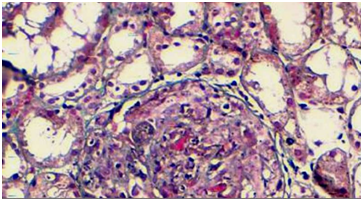

The digestive symptomatology associated with a nephrotic syndrome made suspect in the first place a vasculitis of the small vessels in particular a HSP. Anti-nuclear antibodies were negative. The serum IgA level was normal at 1.3g/L (N: 0.7 to 3.12g/L). A renal biopsy was performed showing a proliferation of mesangial cells and the presence in immunofluorescence of mesangial and pericapillary deposits of immunoglobulins. Given the severity of renal and digestive insufficiency, corticosteroid therapy at a dose of 1mg/kg/day by intravenous route was started with an oral relay on the seventh day. The patient had benefited during the first 4days from a total parenteral nutrition. He also received a blood transfusion and proton pump inhibitors. The evolution of the digestive damage was favorable. However, kidney damage was not recoverable with the need for periodic hemodialysis (Figure 2).

Figure 2 renal biopsy was performed showing a proliferation of mesangial cells.

Skin or renal biopsies with histological study confirm the diagnosis of HSP. In renal biopsy, the anatomopathological study with immunofluorescence reveals glomerular nephropathy with deposits of mesangial and/or parietal immunoglobin A, characteristics of HSP.5 The treatment of HSP with digestive disorders is essentially based on an exclusive parenteral diet. In kidney damage, corticosteroids, immunosuppressants present the basics of treatment.15–17 The evolution is generally rapidly reversible without sequelae. The prognosis is linked to kidney damage and the possibility of new attacks.